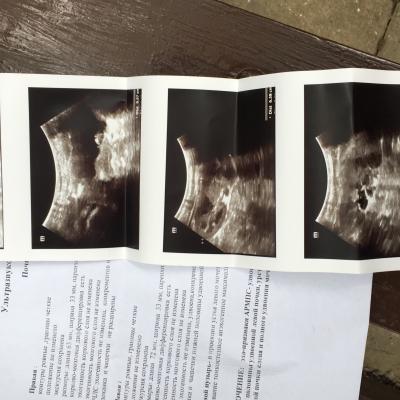

Здравствуйте, у ребёнка в месяц сделали Узи в заключении написали пилокаликоэктозия почки и каликоэктазия почки, сдаём мочу. В три месяца делаем контроль, (в поликлинике) уже они не видят эктозий, видят удвоенную почку.так же сдаём мочу, вроде все нормально. Далее в 11 месяцев сдаю мочу, а там лейкоциты 25, белок 0,066. В детском отд делают цефтреаксон, пьём канефрон, делают Узи и пишут удвоенная почка и косвенные признаки пиелонефрита. Пошли к платному урологу на хорошее Узи прилагаю заключение. Что нам делать с таким диагнозом? Нужна ли операция? Если нужна, то с какого возраста делают такие операции?